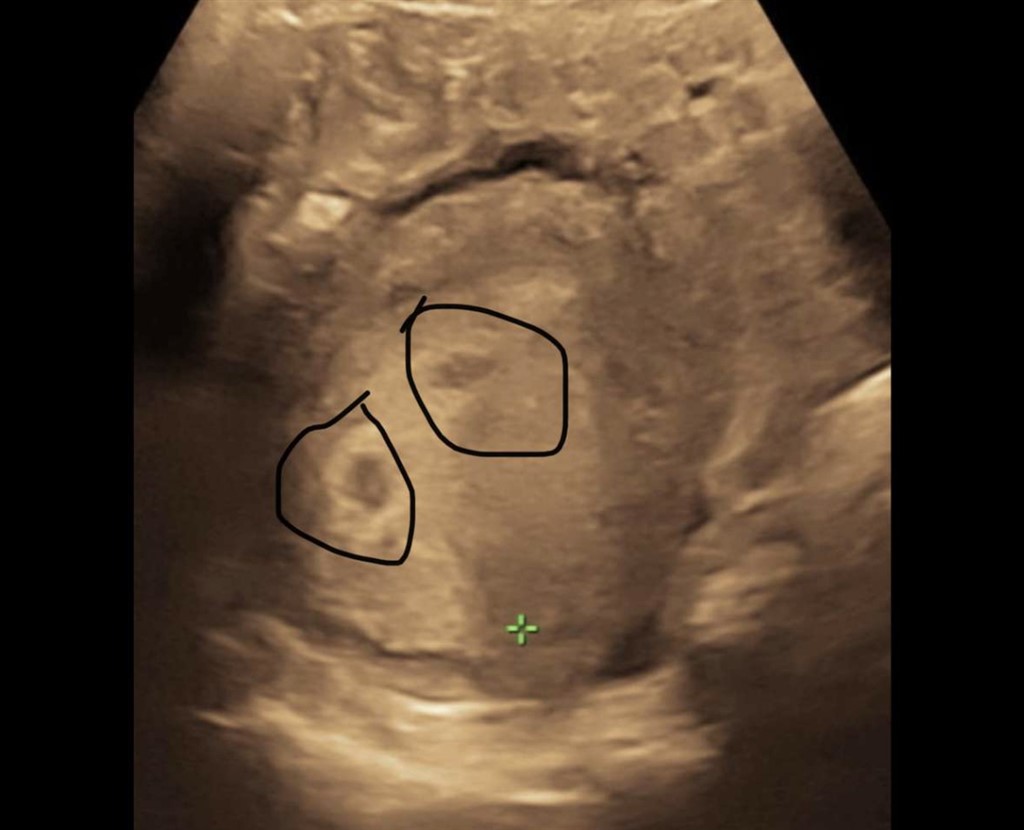

Var til tidlig scanning. Hun mente jeg nok var 5+2 måske.

men er der en eller to ?? Kun nogle gange nr 2 sorte område dukkede op, som jeg forstod det ?

Sådan et billede med to sorte cirkler havde jeg også 4+5, men der var kun en baby Min gynækolog sagde, at det var ret almindeligt at se så tidligt i scanninger, hvor det enten er noget vævsrest, blodansamling eller der KAN være anlæg til en ekstra (oftest tom) sæk, og at denne sæk i langt de fleste tilfælde ikke udvikler sig. Ved en scanning to uger senere var den ene sorte cirkel væk (og jeg havde ikke haft nogen blødning eller lign.)

Så mon ikke det samme er gældende ved den her scanning - bare før du "stresser"/glæder dig over to cirkler

Min gynækolog kaldte sorte plet nr to madpakken til baby

Jeg har haft to sorte “huller” i begge mine graviditeter og der kom kun et barn ud hver gang jeg har fået af vide at det er resterne af madpakken som embryoen får næring af indtil moderkagen virker